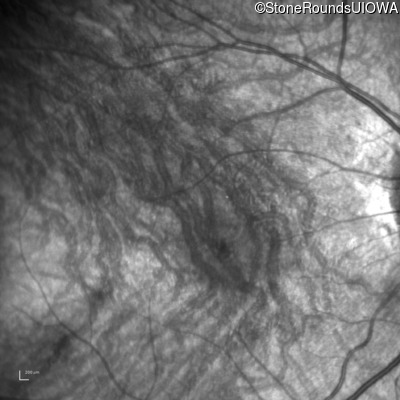

Infrared Fundus Photograph - Right - 10/300 sc

Exemplar